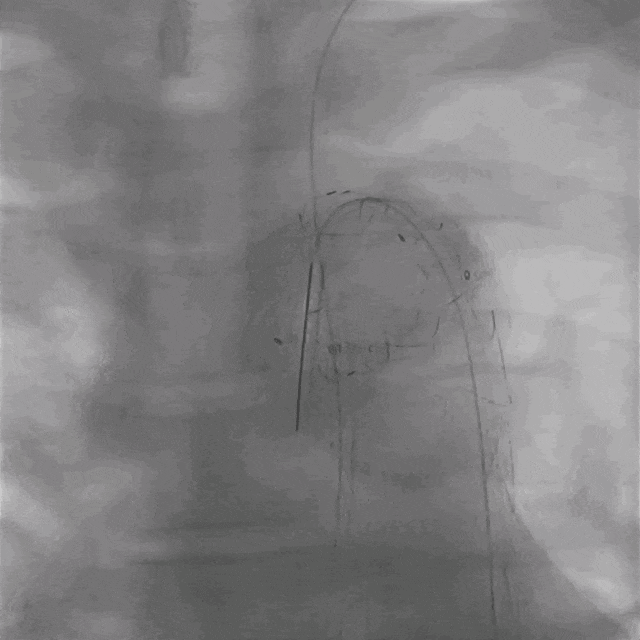

03. 左侧肱动脉采用0.035"泥鳅导丝硬头配合支撑导管顺利破膜,引入4mm球囊予以开窗处扩张。

调节支撑导管垂直于覆膜

泥鳅导丝硬头顺利破膜